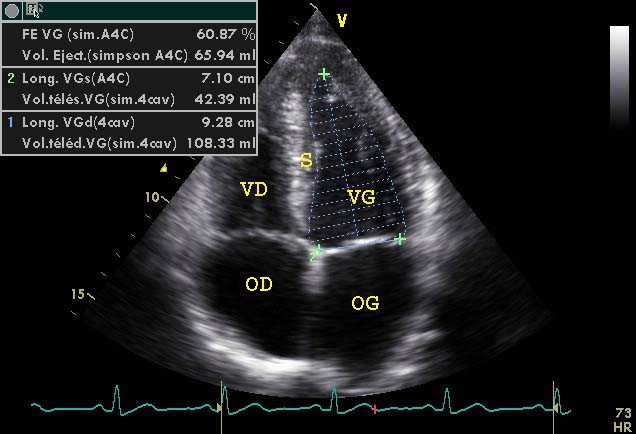

...en mode bidimensionnel: le capteur est positionné au niveau du choc de pointe. Par convention, les cavités gauches sont présentées sur la droite de l'écran. Cette coupe permet, en quelques secondes, d'appréhender la taille des 4 cavités et la fonction contractile des ventricules. Les mouvements du septum interventriculaire sont importants à considérer car ils rendent comptent des variations instantanées du gradient de pression VG-VD. Cette coupe est particulièrement utile pour évaluer la fonction pompe, car à partir des mesures de surfaces télédiatolique et télésystolique VG par planimétrie, le modèle mathématique de Simpson permet le calcul des volumes et donc de la fraction d'éjection (FE = (VTD-VTS)/VTD 66±6%)